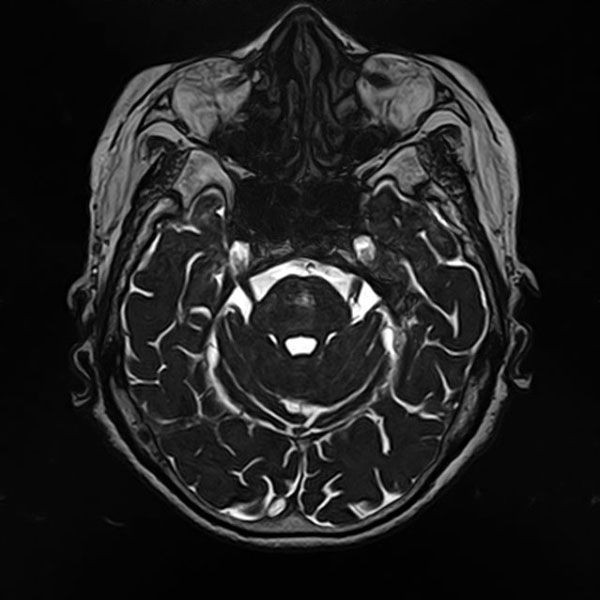

手術前

(MR1)